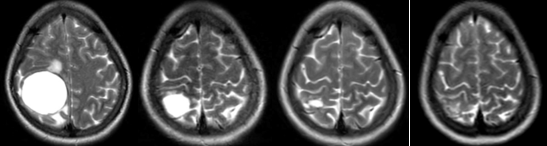

Bệnh nhân được chụp cộng hưởng từ sọ não, phát hiện khối u vùng đỉnh chẩm phải kích thước 39x46x43 mm, theo dõi tổn thương thứ phát

Hình 1. Hình ảnh cộng hưởng từ sọ não ngày 27 tháng 10 năm 2022 khối u não vùng đỉnh chẩm phải (mũi tên).